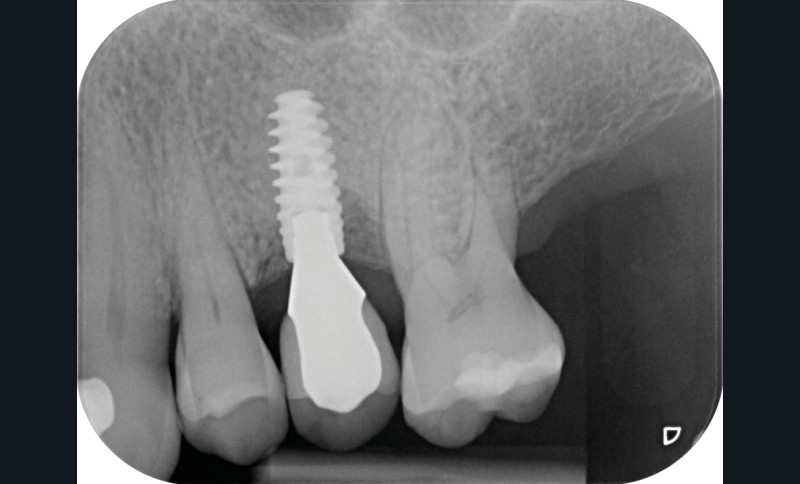

Chez cette patiente, le traitement de la péri-implantite a été réalisé à l’aide d’une technique de régénération osseuse guidée péri-implantaire, dont l’indication a été principalement motivée par la morphologie du défaut osseux. Au-delà de la maîtrise du geste chirurgical, le bon résultat obtenu à trois ans est intimement lié à sa coopération en termes de suivi et de contrôle de plaque.

13 et 14. À 3 ans, une régénération osseuse satisfaisante et un bel aspect des tissus péri-implantaires sont observés. Les poches font 3 mm en mésial, distal et palatin, et 2 mm en vestibulaire. Il n’y a pas de saignement au sondage.